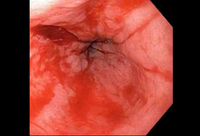

A laceração de Mallory Weiss após aplicação de clipe do tipo "through-the-scope" resulta em hemostasia

Do acervo pessoal de Douglas Adler; usado com permissão